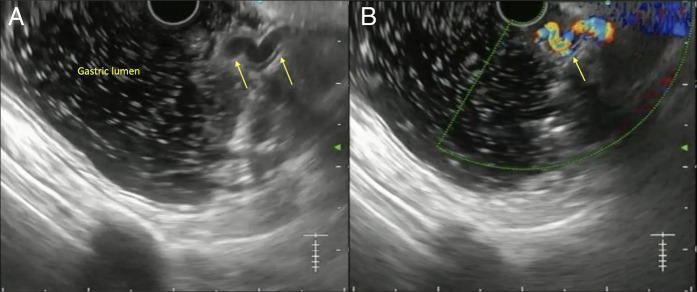

Expanding Horizons of Vascular Interventions: Endoscopic Ultrasound-Guided Angioembolization for a Refractory Upper Gastrointestinal Bleed From a Gastric Dieulafoy Lesion.